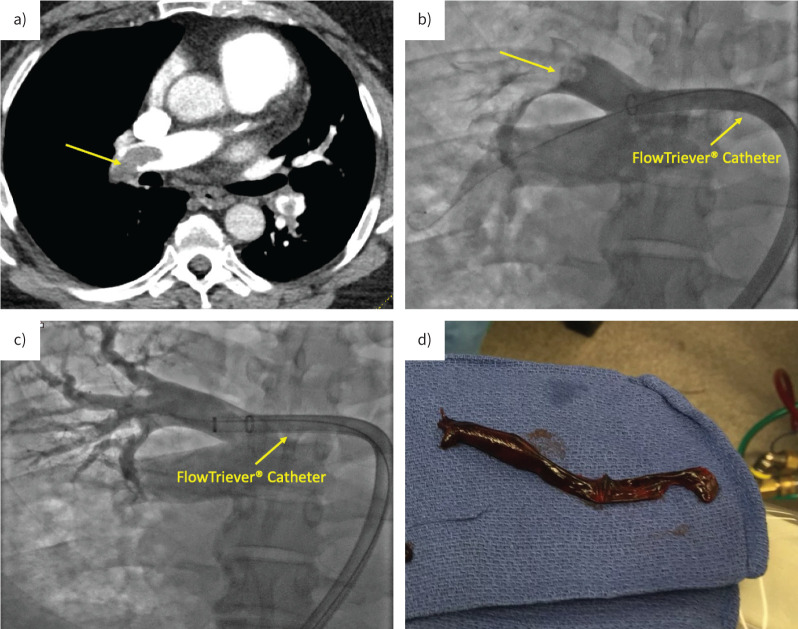

Therapeutic anticoagulation is the mainstay therapy in acute pulmonary embolism (PE), however, select patients benefit from emergent reperfusion to prevent or rescue acute right ventricular failure and haemodynamic collapse. Compared to other leading causes of cardiovascular mortality such as myocardial infarction and stroke, there is a substantial paucity of literature informing on advanced therapies in PE. Recent years have seen significant evolution in the armamentarium available for PE care with the uptake of several endovascular treatment modalities and increased use of mechanical circulatory support. While several ongoing randomised controlled trials may alter the therapeutic landscape and approach to PE management, at present, we are left with multiple selections with limited guidance. In this review, we discuss the latest therapeutic options available for acute PE and offer an approach to their implementation.